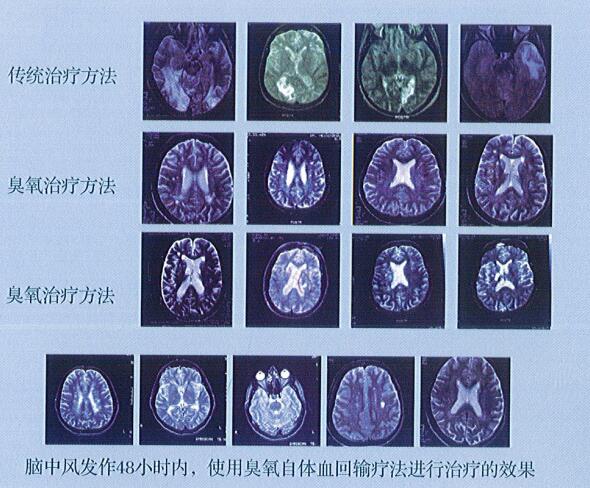

治療腦中風(fēng)

通過(guò)醫(yī)用臭氧治療儀產(chǎn)生精確度極高的定量濃度的臭氧經(jīng)自體血回輸療法,在發(fā)病48小時(shí)之內(nèi)接受治療的患者可大幅度降低發(fā)生偏癱等后遺癥的機(jī)率,而且治療周期和費(fèi)用都遠(yuǎn)低于傳統(tǒng)療法。臭氧治療對(duì)中風(fēng)康復(fù)期患者也有非常好的療效。其原理是: